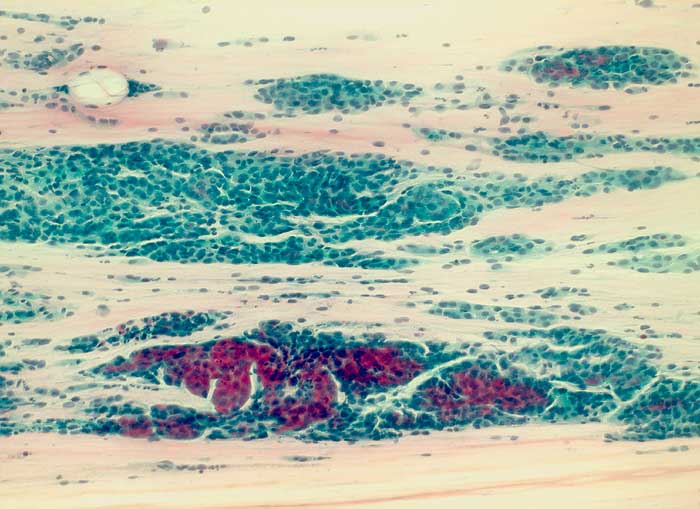

seröses papilläres Adenokarzinom des Endometrium

Portioabstrich: Der Ausstrich enthält auffallend viele Zellen mit zum teils tapetenförmigen, teils auch angedeutet papilliformen Verbänden. Die Zellen sind etwas grösser als Basalzellen des Plattenepithels und besitzen deutliche polymorphe Kerne. Zytoplasmaleib uncharakteristisch zyanophil.

Histologie: serös papilläres Endometriumkarzinom

Zytologische Diagnose: Massenhaft Verbände von Epithelien mit Kernatypien.

Im vorliegenden Befund lässt sich nicht sicher entscheiden, ob die Zellen aus der Portio oder aber aus dem Endometrium stammen. Histologische Abklärung ratsam.

100